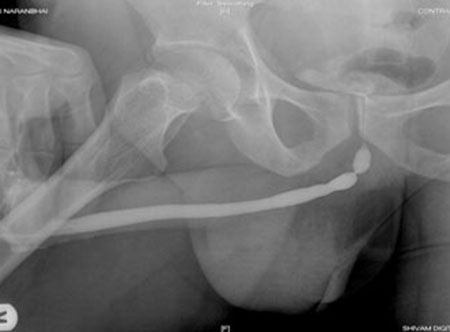

• Special X-rays may be taken whilst you pass urine, which can show the site and severity of a stricture.